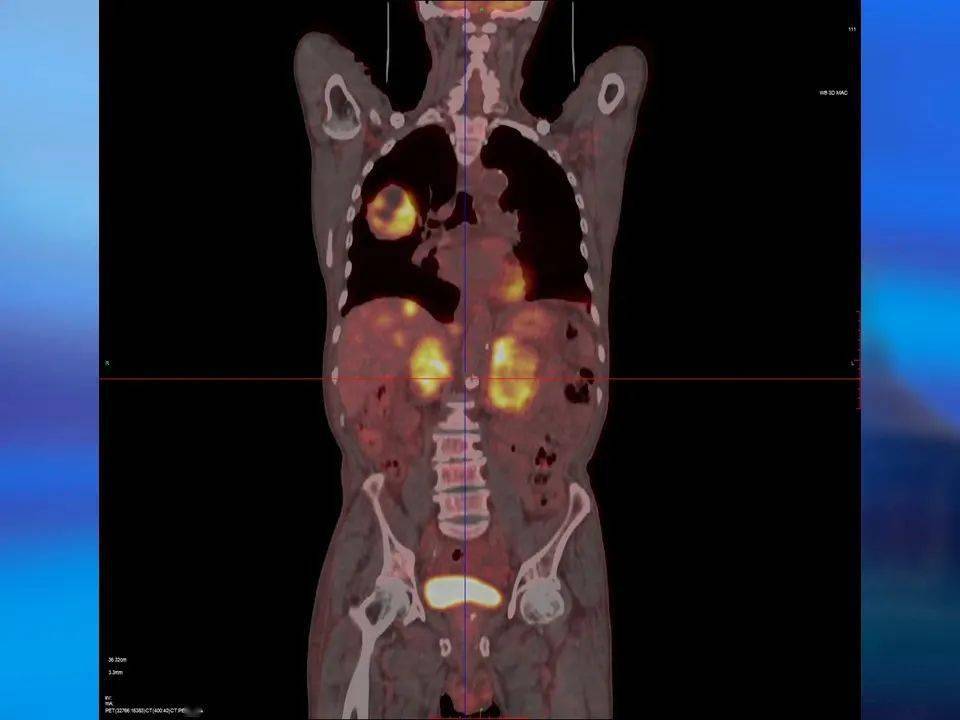

发布高建英主任petct在肿瘤远处转移中的临床应用